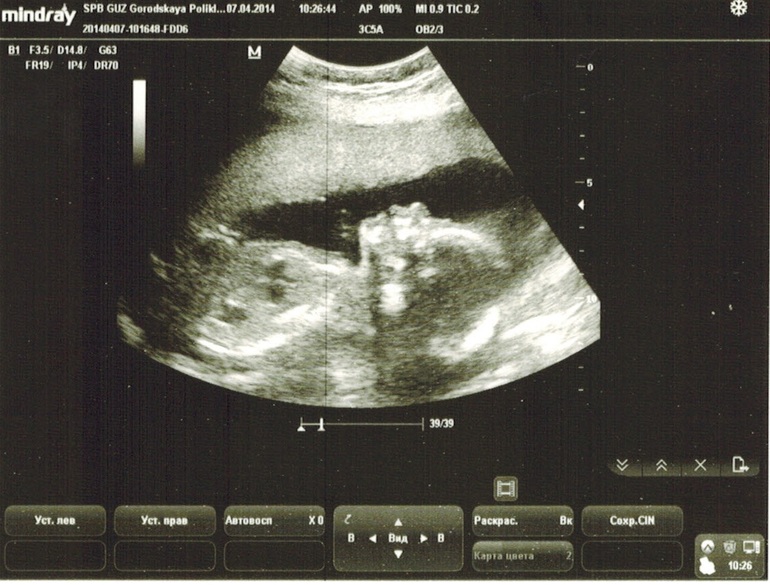

Узи показало - Девочку!

Ну, вот наконец я узнала, кто у нас будет :)

Доченька-лапочка